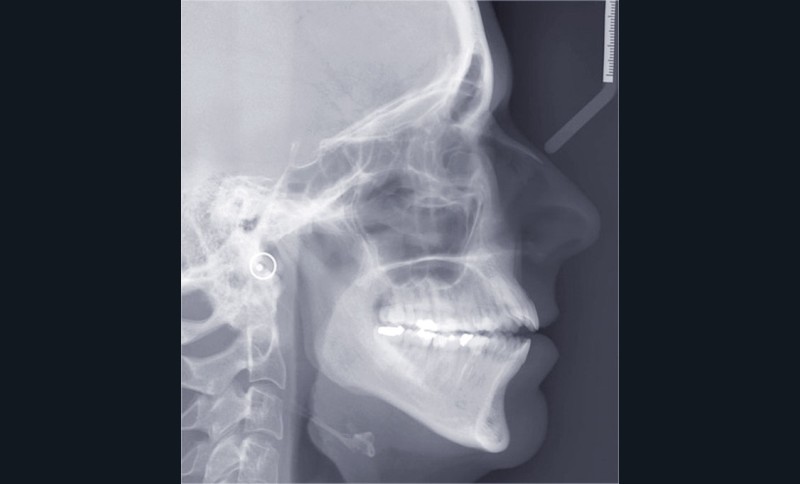

Il a été décidé de mettre en œuvre une thérapeutique avec brackets vestibulaires Damon afin d’optimiser l’expansion des arcades, la fermeture de la béance et la réduction du sourire gingival latéral qui perturbe l’esthétique du sourire de la patiente.

L’esthétique faciale de la patiente s’est nettement améliorée (fig. 7, 8, 9 et 10). On remarquera la réduction du sourire gingival…